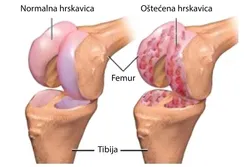

Gonartroza je degenerativno oboljenje kolena koje nastaje kao posledica propadanja hrskavice zgloba, usled čega nastaje formiranje koštanih šiljaka-osteofita.Tako izmenjena struktura tkiva doprinosi stvaranju upale i bola koja stvara velika ograničenja u samom zglobu. Hrskavica zgloba se regeneriše onoliko koliko se troši tokom redovne umerene fizičke aktivnosti, medjutim kada je fizička aktivnost pojačana kao npr. kod sportista gde su prisutne stalne mikrotraume, onda je obnavljanje hrskavice smanjeno.Postoji više faktora rizika koji pospešuju razvoj gonartoze:

Svi ovi faktori doprinose razvoju progresivnih degenerativnih promena u kolenu.